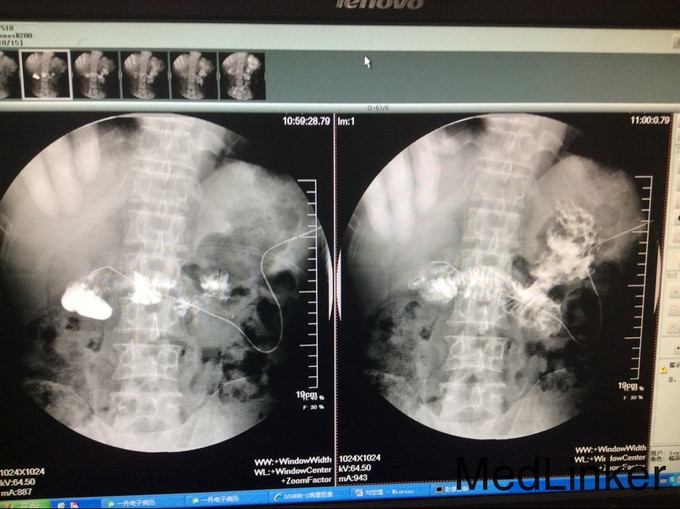

主诉:方向盘伤,胰头十二指肠破裂,肝十二指肠韧带撕裂伤术后8月,复杂肠漏1例。 2.现病史:患者因8月前因腹部外伤,当地医院行剖腹探查术,术中发现胆管、胰管、十二指肠损伤,肠系膜上静脉撕裂,行胰十二指肠切除,胰肠+胆肠+胃空肠Y吻合。术后出现重度感染休克、外伤性胰腺炎,予以腹腔引流术+空肠造瘘置营养管术,行抗休克、抗炎治疗,现术后8月腹腔引流管持续引流出胆汁及肠液,经引流管造影可见造影剂流入肠管,行上消化道造影未提示胃及肠管穿孔。

入院查血: Blood-Rt(五分类): 白细胞 6.97*10^9/L,红细胞 3.84*10^12/L,血红蛋白 122 g/L,红细胞压积 37.3 %,血沉 42 mm/h 查体:无特殊异常,腹腔引流管偶有黄褐色浑浊液体流出,量约50-80ml,腹软,无压痛、反跳痛,二便正常。 辅检:上腹部CT提示:胆肠吻合口一直径约2cm结石 辅助检查见上图

漏口位置,依据上消化道钡餐造影未见消化道穿孔,而从腹腔引流管处注入碘水造影可见肠管及隐约胃形显示,估计漏口位置为胰腺空肠及胆管吻合处肠管漏口, CT提示:胆道结石,尝试拔管后漏口无法愈合,再次予以腹腔引流置管。 我们分析漏口无法愈合的原因为胰液及胆汁对自身组织的消化,术中胆肠吻合口处放置T管,及胰腺空肠段放置引流管,引流肠液,目的为减轻消化液对漏口的影响,术后原漏口愈合,但出现新唇状漏,采用T管经皮下隧道引流 ,原皮肤漏口缝闭,同时加用负压吸引。 讨论2点: 1.该病人初次少量胆漏合并胆道结石时是否需要手术治疗? 2.再次出现唇状漏时,患者消化液外漏引起局部皮炎,皮肤伤口周围组织腐蚀严重,采用T管经皮下隧道引流,能否起到良好的治疗效果?